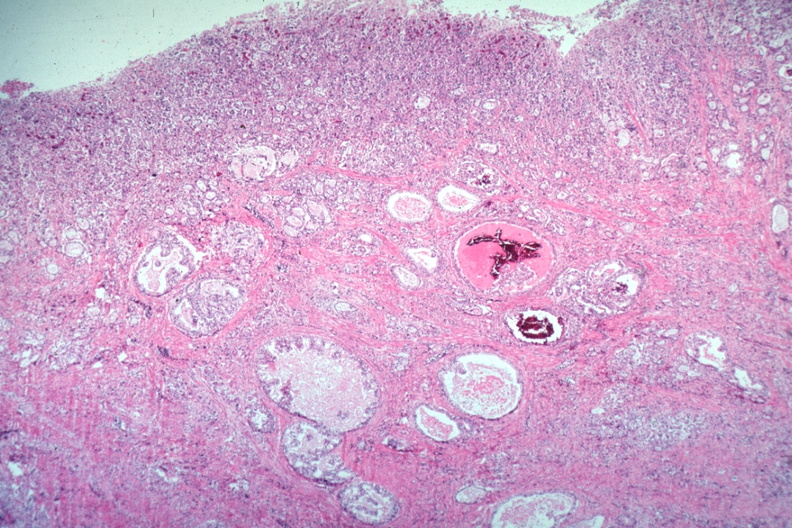

HISTOLOGY: GASTROINTESTINAL: Stomach: Adenocarcinoma: Micro low mag H&E mucosal and submucosal infiltration varying morphology a one cm sessile polyp prepyloric with metastasis to hepatic node an incidental finding died with promyelocytic leukemia